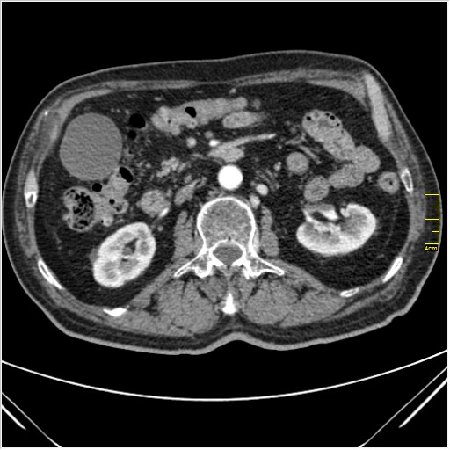

Мужчина 62 года с желтухой

Опухоль головки поджелудочной железы, расширение холедоха и панкреат. протока (Double Channel sign)

Карциномы панкреас гиподенсны на КТ с болюсом, т.к. содержать много соединительной и фиброзной ткани, в отличие от нормальной ткани железы, которая (как любая железа) хорошо васкуляризирована. Поэтому если видим в панкреас солидное гиподенсное образование - всегда настораживает на предмет рака. Второй момент: обязательная оценка взаимоотношения опухоли к ВБА и ВБВ, на предмет оценки операбельности.